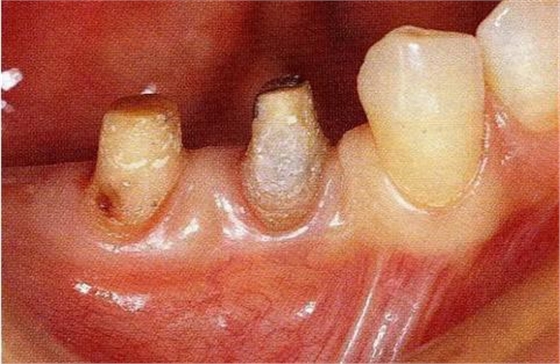

圖18-4▲正畸結(jié)束后6個(gè)月,骨外科處理后的狀態(tài)。附著齦嚴(yán)重不足。

圖18-5▲骨外科處理后牙槽骨平坦,同時(shí)為了獲取附著齦進(jìn)行游離齦瓣移植。

圖18-6 ▲術(shù)后6個(gè)月的狀態(tài),獲得足夠的附著齦。